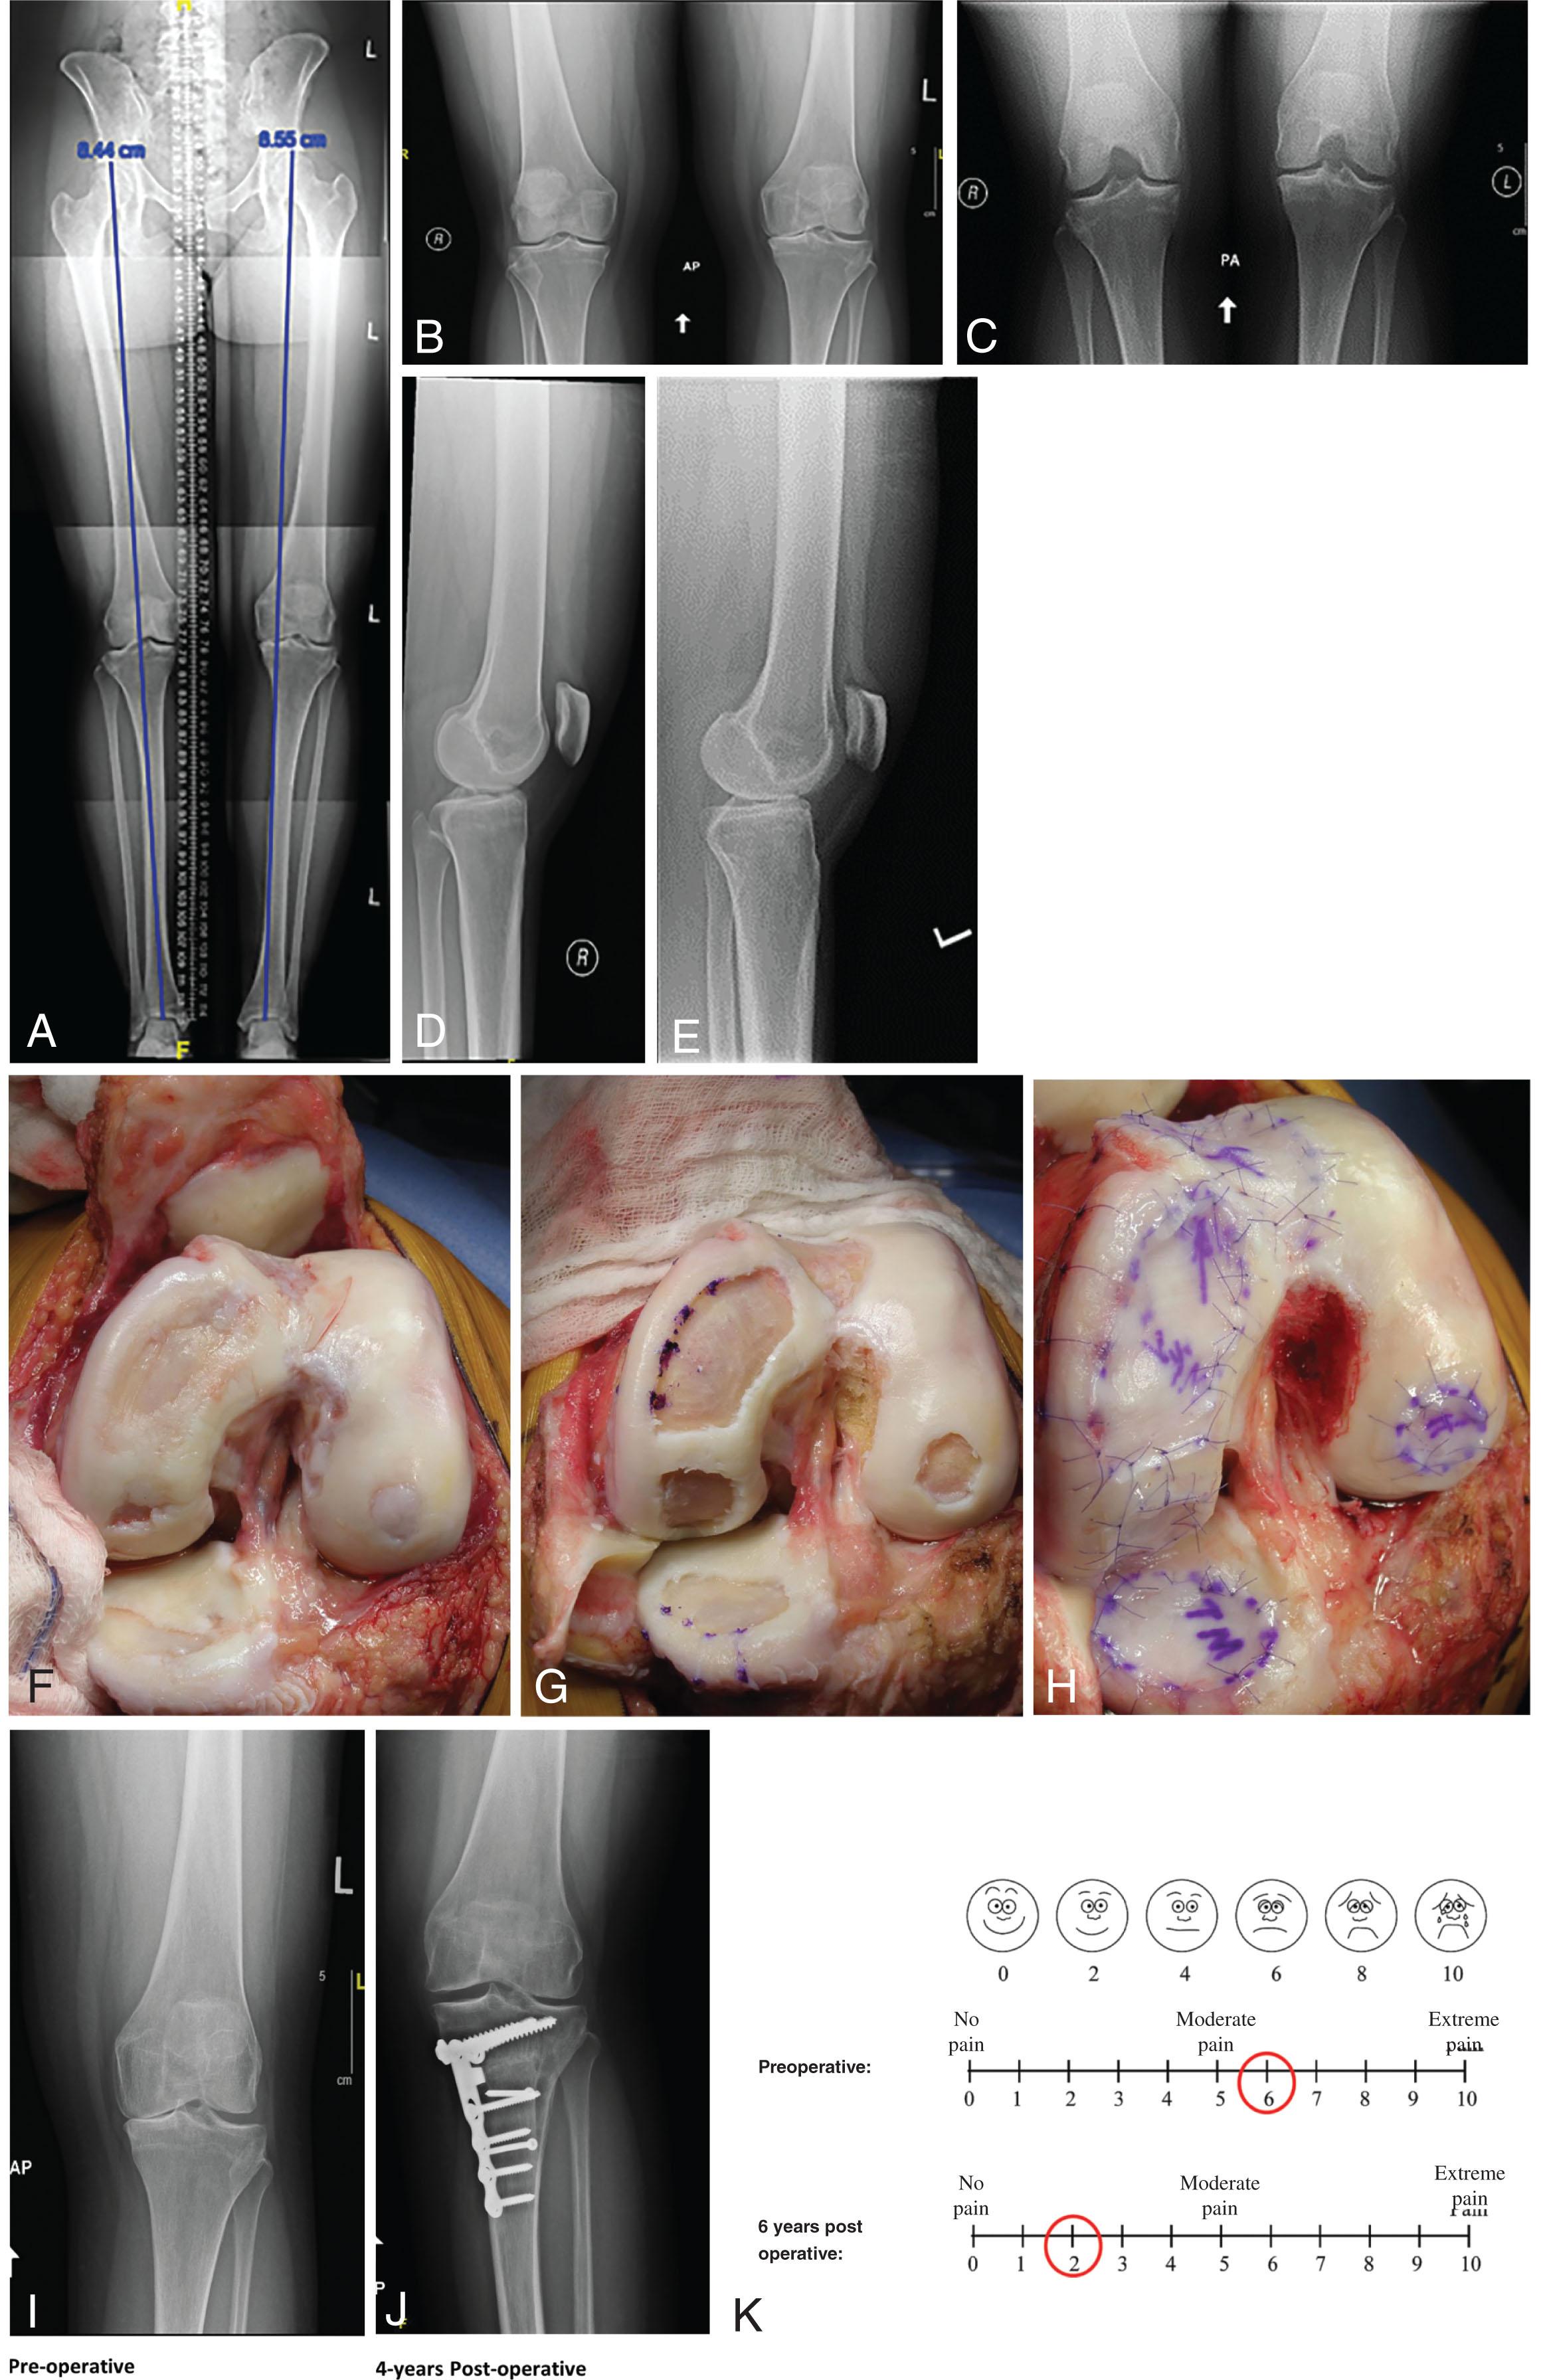

Varus alignment is present on the limb alignment x-ray images with the mechanical axis line falling through the center of the medial tibial plateau. There is narrowing of medial cartilage joint spaces ( Fig. 15.2A–E ).

Fig. 15.2, (A) Long alignment x-ray image demonstrates weight-bearing axis to fall through the center of the medial joint compartment. (B) Standing AP x-ray image demonstrates loss of joint space anterior in the medial compartment. (C) Standing PA x-ray image demonstrates well-preserved posterior medial joint compartment. (D and E) Well-preserved patellofemoral joint space of both knees. (F) Large articular defects noted on the medial femoral condyle, medial tibial plateau, lateral femoral condyle, and trochlea. The exposure is facilitated by a tibial tubercle osteotomy that has been flipped up and a takedown of the medial meniscus. (G) Radical debridement of all the articular cartilage is performed back to stable intact full-thickness cartilage. The blue dots represent the location of transosseous drill holes made to secure the collagen membrane and chondrocytes using a small C-wire on a wire driver. The sutures are passed by straightening out the P3 cutting needle with a needle driver. (H) Final appearance of c-ACI after microsuturing, sealing the areas with fibrin glue, and injecting autologous cultured chondrocytes to fill the defects. The medial meniscus is then brought back to the intermeniscal ligament in near full extension and repaired with transosseous sutures through the medial meniscus anteriorly through the metaphyseal bone with a tapered needle no. 1 Vicryl suture. The tibial tubercle is then repositioned to center patellar tracking and fixated with two anterior to posterior lag screws followed by the medial patellofemoral ligament reattached to the mid-patellar pole and the lateral retinaculum being lengthened. Postoperative range of motion is instituted the morning after surgery using patellar mobilizations with manual therapy and a continuous passive motion machine. Touch weight-bearing for 6 weeks was followed by progressive weight-bearing to full body weight at 10 weeks with a medial compartment unloader braces. Because of the lateral femoral condyle defect the axial alignment is not overcorrected into the lateral compartment but just brought back to the midline. (I) Preoperative standing AP x-ray image shows loss of the anterior medial joint space with bone-on-bone changes. (J) Four-year postoperative weight-bearing x-ray image showing complete restoration of the medial joint compartment. It is a full weight-bearing AP x-ray image with mechanical axis corrected to the midline and not into the lateral compartment because of the lateral femoral condyle transplant. (K) VAS scores preoperative and postoperative.

ACI (autologous cultured chondrocytes) using four vials of Carticel (Genzyme, Cambridge, MA, USA) with Bio-Gide membrane (Geistlich Industries, Wolhusen, Switzerland) was performed to the medial femoral condyle anterior (40 × 20 mm), posterior (25 × 15 mm), medial tibial plateau (25 × 15 mm), lateral femoral condyle (15 × 15 mm), trochlea (30 × 20 mm) combined with an opening wedge tibial valgus osteotomy and a tibial tubercle anteromedialization osteotomy ( Fig. 15.2F–H ).

Four years after surgery, the medial joint space is restored as seen in postoperative AP x-ray examination ( Fig. 15.2I–J ). Six years after surgery, the patient is doing well with a 96.4 KOOS score (preoperative 61.3) ( Table 15.1 ), VAS score of 2 (preoperative 6) ( Fig. 15.2K ), and modified Cincinnati rating of 10 (preoperative 5) ( Table 15.2 ). The patient reports full return of her knee function with minimal discomfort and has resumed recreational activities, including hiking, yoga, and even sports, and work without pain.